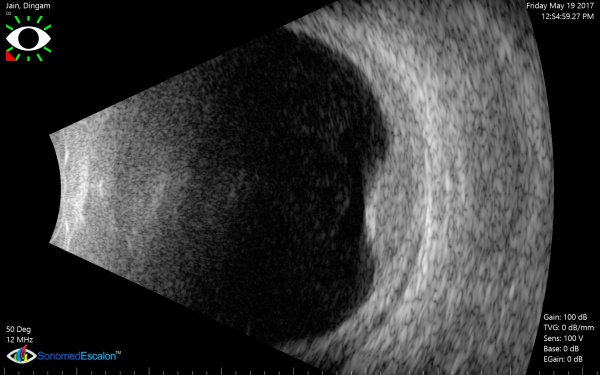

[The funnel RD is attached to the disc and is not showing after-movements with ocular movements.]